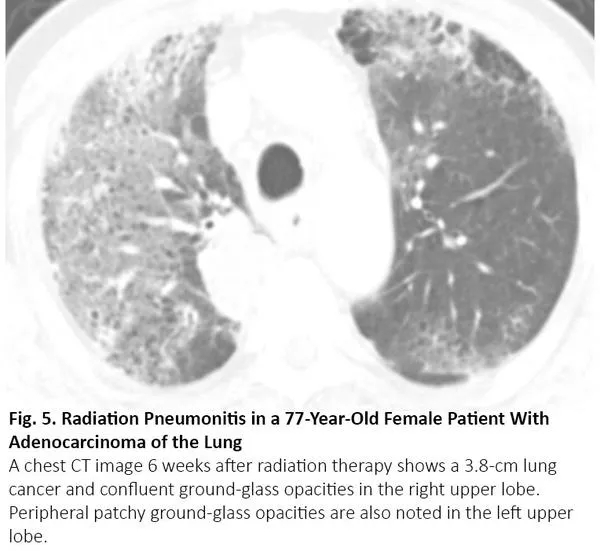

放疗结束后4~12周内可能发生放射性肺炎,有时更晚15。因为放射性肺炎通常发生在照射野,发生于局部,因此在大多数情况下,放射性肺炎与COVID-19肺炎的影像鉴别很简单。然而,当肺炎呈弥漫性分布时,可能无法将放射性肺炎与COVID-19肺炎区分(图5)。

图5. 一位77岁肺腺癌女性患者出现放射性肺炎